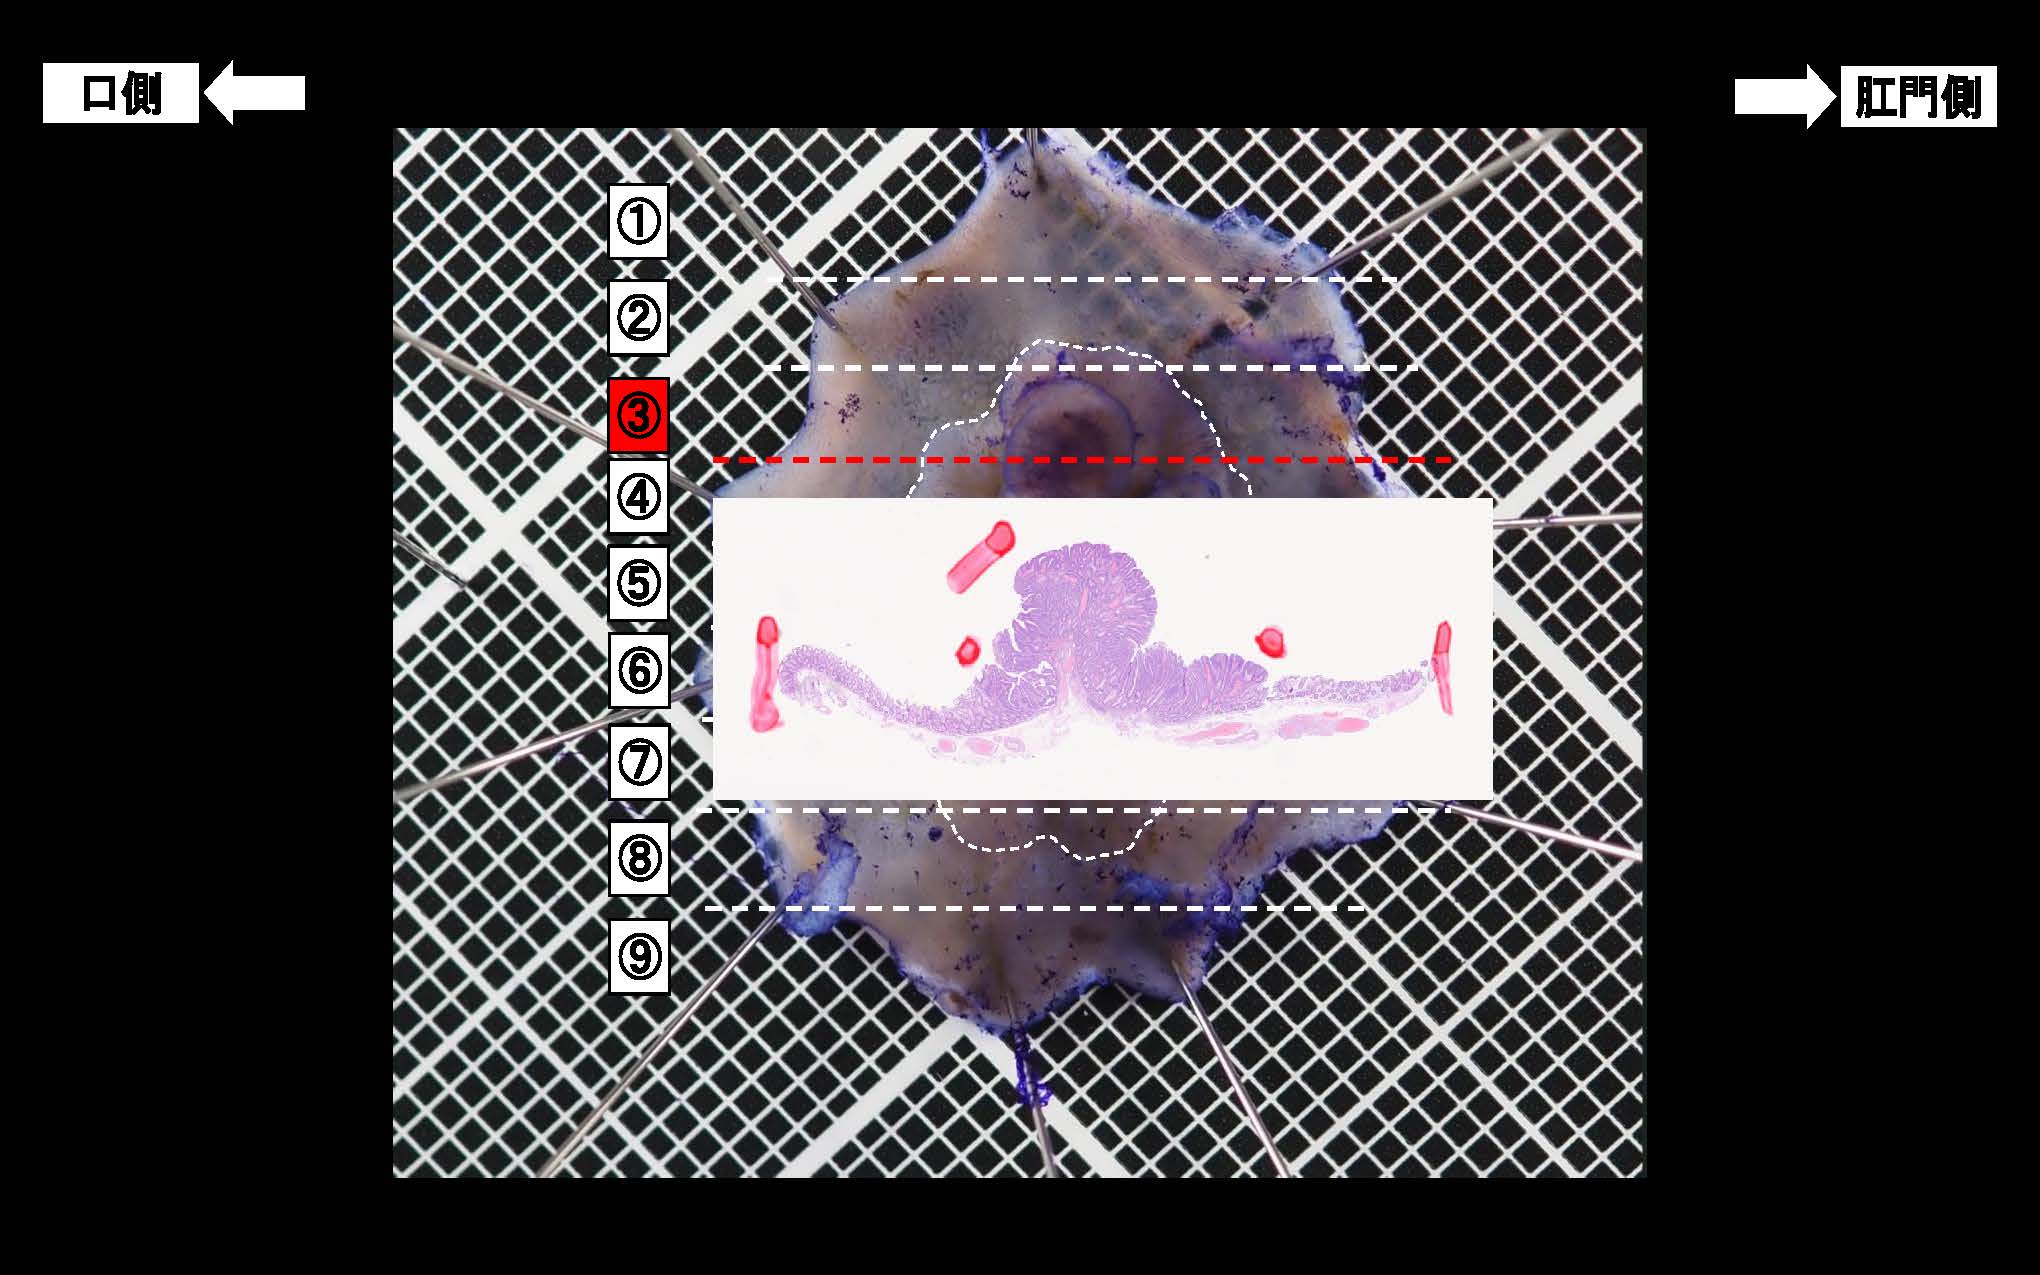

消化管Mapping~大腸~ 2025.6.11

消化管Mapping

消化管Mapping~大腸~

消化器内科

内視鏡検査・治療